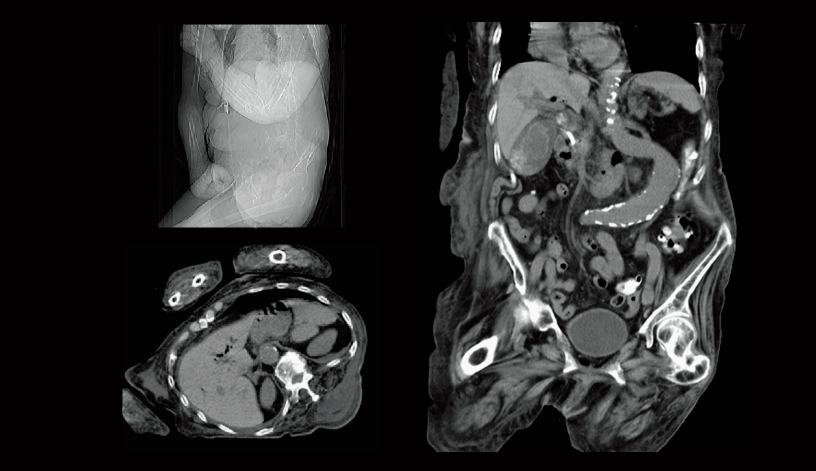

Renal cell carcinoma (80 kV)

Abdominal aortic occlusion